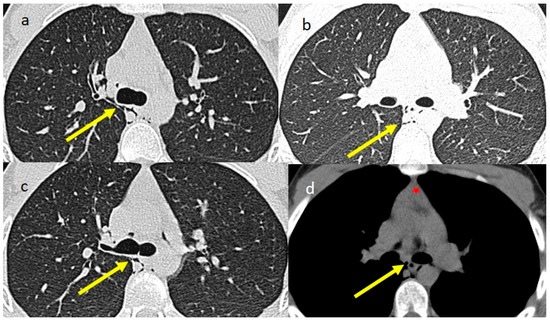

2. Case Presentations